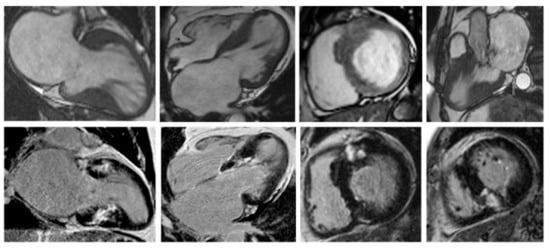

Nonetheless, due to increased temporal resolution, ability to comprehensively evaluate all heart structures and capacity to characterize myocardial tissue and unravel fibrosis, CMR has currently became the gold-standard imaging tool for diagnosing and assessing patients with HCM. CMR is able to accurately quantify heart chambers’ volumes and dimensions and also both LV and right ventricle (RV) systolic functions. Moreover, CMR is the only large-scale available noninvasive imaging tool capable of tissue characterization. This aspect has a tremendous role in patients with HCM since it can identify and accurately quantify both myocardial replacement and diffuse fibrosis and it can also exclude other infiltrative cardiomyopathies such as amyloidosis [27]. CMR summarized in Table 1. Specific cases of HCM assessed by CMR are presented in Figure 2, Figure 3 and Figure 4.

Figure 2. Contrast-enhanced CMR in a 50-year-old male patient with hypertrophic cardiomyopathy (from the own collection of the authors). (Upper row): b-SSFP cine images in two chambers, four chambers, short axis and three chambers, respectively. There is asymmetrical LV hypertrophy, with a maximum thickness of 20 mm at the basal anterior wall. The LV is not dilated and the LVEF is within normal limits (59%). There is systolic anterior motion of the mitral valve, resulting in acceleration of the systolic flow in the LV outflow tract. (Lower row): LGE imaging shows patchy myocardial fibrosis of the hypertrophied segments. Abbreviations: b-SSFP, balanced steady-state free precession; CMR, cardiac magnetic resonance imaging; LVEF, left ventricle ejection fraction; LGE, late gadolinium enhancement; LV, left ventricle.

Figure 3. Contrast-enhanced cardiovascular magnetic resonance imaging in a 32-year-old male patient with a history of hypertrophic cardiomyopathy due to a pathogenic mutation in MYBPC3 gene (c.772G>A) (from the own collection of the authors). The current findings are compatible with a phenotype of burn-out HCM. (Upper row): b-SSFP cine images in two, four and three chambers, and short axis, respectively. The LV is severely dilated (166 mL/m2) with severe systolic dysfunction (LVEF 22%). Currently, there is no LV outflow tract obstruction, although an obstructive phenotype was diagnosed 10 years before. (Lower row): LGE imaging shows extensive heterogeneous replacement myocardial fibrosis at the level of the interventricular septum, anterior and inferior LV walls, respectively. Also note the fibrosis of the papillary mitral muscles. Abbreviations: b-SSFP, balanced steady-state free precession; CMR, cardiac magnetic resonance imaging; LVEF, left ventricle ejection fraction; LGE, late gadolinium enhancement; LV, left ventricle.

Figure 4. Contrast-enhanced CMR in a 50-year-old female patient with a history of hypertrophic cardiomyopathy with LV apical aneurysm (from the own collection of the authors). (Upper row): b-SSFP cine images in four, three and two chambers, and short axis, respectively. The LV is dilated (110 mL/m2) with severely impaired systolic function (LVEF 25%). There is asymmetrical LV hypertrophy with a maximum wall thickness of 28 mm at the level of the interventricular septum. Note the large apical aneurysm with a maximum diameter of 40 mm and thin walls. (Lower row): LGE imaging shows transmural fibrosis of the LV apical aneurysm and a small focal intramyocardial scar at the level of the basal infero-lateral wall. The total percent of fibrosis is 16% of the LV myocardium. No thrombus is seen inside the apical aneurysm. Abbreviations: b-SSFP, balanced steady-state free precession; CMR, cardiac magnetic resonance imaging; LVEF, left ventricle ejection fraction; LGE, late gadolinium enhancement; LV, left ventricle.